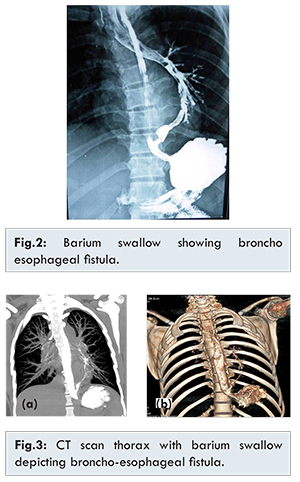

The investigation of choice in a suspected trachea-esophageal fistula is barium swallow. Hence barium swallow was done. Barium swallow showed broncho-esophageal fistula. Fistulous tract was seen connecting lower 3rd of esophagus to left lower lobe bronchus with retrograde filling of left main bronchus and trachea [Fig.2]. Upper gastro-intestinalscopy showed a small opening around 3 cm above the gastro-esophageal junction. Mucosa around the opening was normal. CT scan thorax with barium swallow was done. It showed reflux of barium into the anterior segment bronchus of left lower lobe from distal esophagus through a fistulous communication at the esophageal hiatus level. There was minimal patchy opacity in left lower lobe [Fig.3].   Bronchoscopy showed bronchial end of the fistula in the left lower lobe bronchus with no signs of inflammation. A final diagnosis of congenital broncho-esophageal fistula was confirmed as investigations did not reveal any cause for acquired fistula.